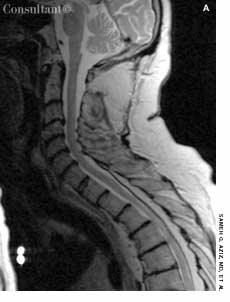

A 13-year-old girl who had leukemia presented to the emergency department with fever; chills; weight loss; fatigue; and a painful, erythematous rash with a central black lesion on the upper thigh. The patient was neutropenic and had been undergoing chemotherapy for 1 week.